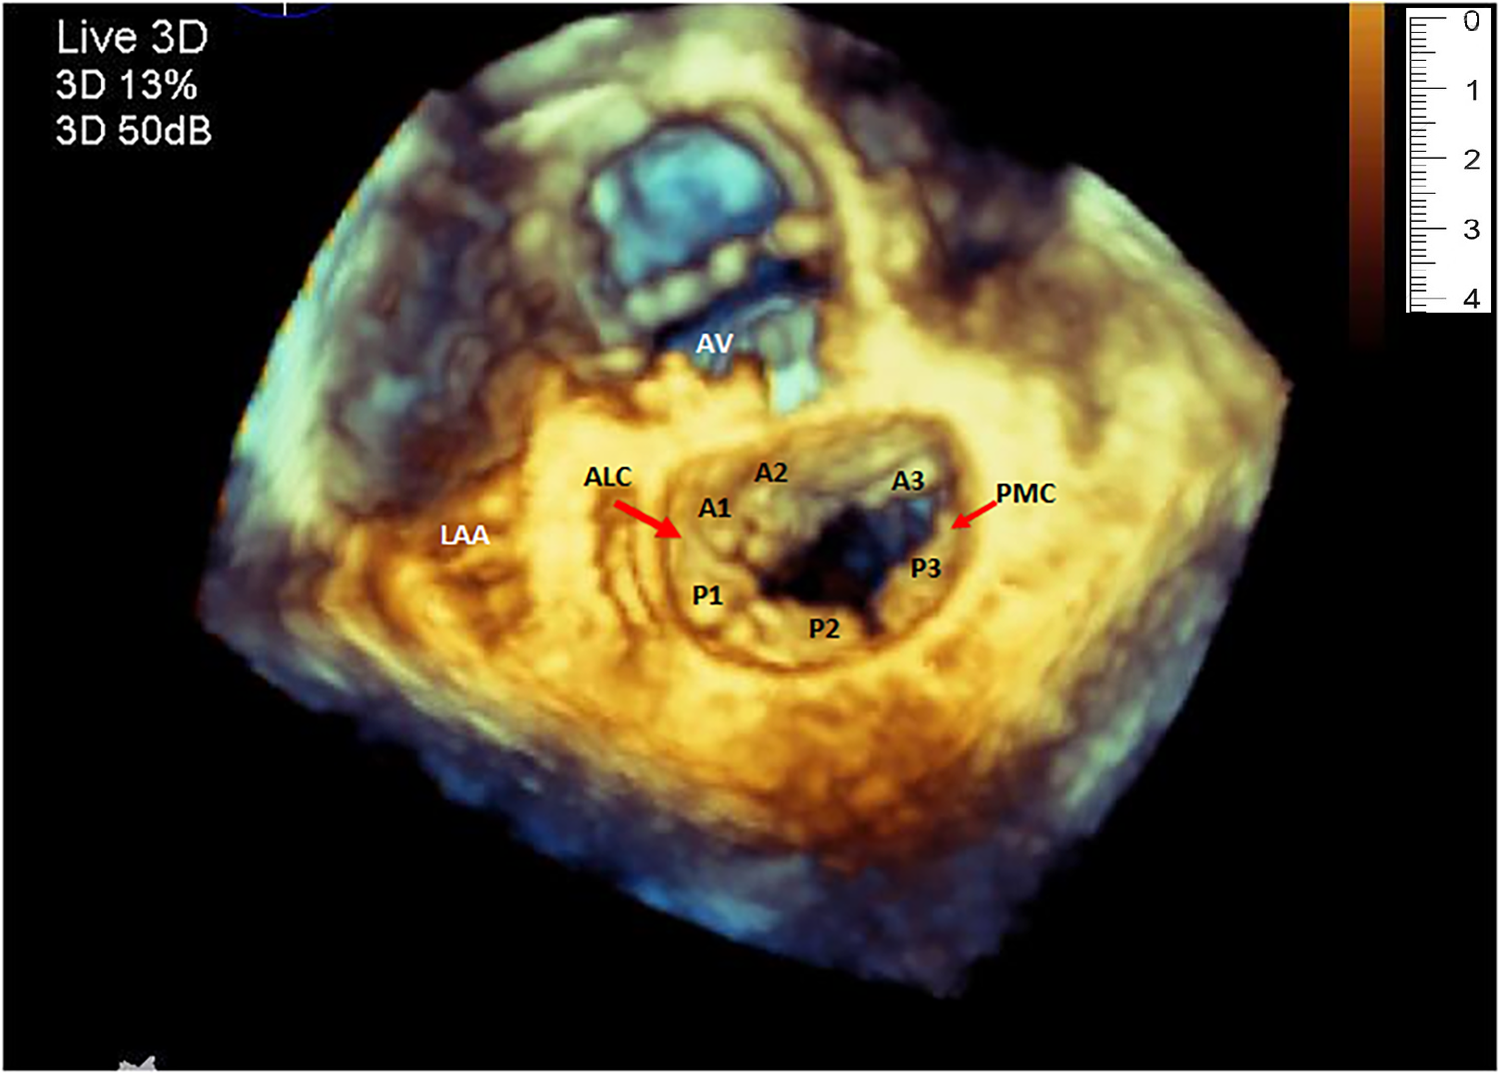

Although the clinical use of 3D Echocardiography has been around for more than two decades, its value in generating 3D models of cardiac structures has not been thoroughly investigated. Echocardiographic 3D data sets of a mitral valve (Figure 1), obtained via the transesophageal window, have been shown to have enough spatial and temporal resolution for clinical use. Successful attempts to 3D print from transesophageal echo for the evaluation of and closure of paravalvular leaks of the mitral valves have been reported (13, 14).

Figure 1

Three-dimensional echocardiography image of the mitral valve showing the normal shape of the annulus, both leaflets and the corresponding segments. (LAA, left atrial appendage; ALC, antero-lateral commissure; PMC, postero-medial commissure).